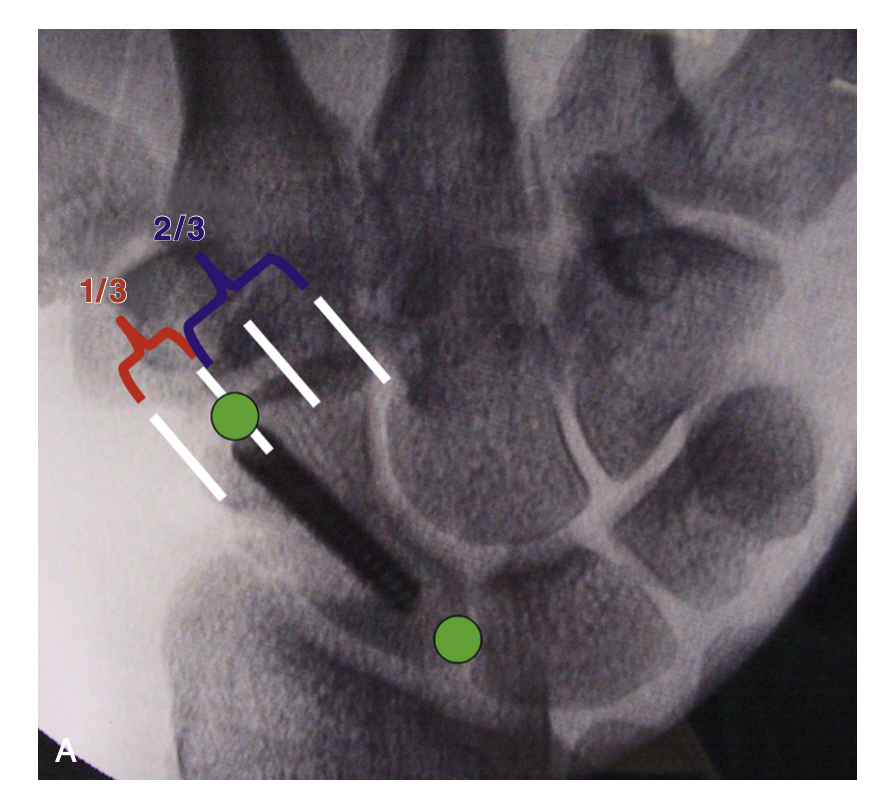

- Durante o ato cirúrgico, o cirurgião de mão utilizará um equipamento chamado radioscopia para guiar a introdução do fio guia e do parafuso. Através desse equipamento e de referências anatômicas, será definida a posição ideal do parafuso. Por exemplo, no plano coronal, um bom parâmetro radiográfico da posição distal do parafuso é o ⅓ da distância do lado radial do pólo distal do escafóide